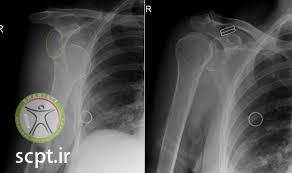

پس از جا اندازی، پزشک معالج از شانه بیمار مجددا رادیوگرافی به عمل می آورد تا از جا افتادن مفصل مطمئن شود. پزشک سپس دست بیمار را با بانداژ بخصوصی به نام بانداژ ولپو به گردن و تنه وی آویزان می کند. این بانداژ حدود ۳-۲ هفته می ماند و سپس حرکات شانه برای ممانعت از محدود شدن شروع می شود. در مدت این چند هفته بیمار باید مرتبا دست، مچ دست و مفصل آرنج خود را حرکت دهد تا از خشک شدن آن ها جلوگیری کند.

گاهی اوقات همراه با دررفتگی مفصل شانه ممکن است شکستگی در گردن استخوان بازو و یا در برجستگی سر استخوان بازو ( توبروزیته بزرگ ) بوجود آید. شکستگی توبروزیته بزرگ Greater tuberosity در اکثر موارد بعد از جااندازی مفصل شانه ، خودبخود جا می افتد. در صورت جا نیفتادن نیاز به عمل جراحی و فیکس کردن قطعه با پیچ می شود. شکستگی گردن استخوان بازو اگر همراه با دررفتگی مفصل شانه باشد معمولا نیاز به عمل جراحی دارد. با استفاده از عمل جراحی شکستگی جااندازی شده و با پیچ و پلاک فیکس می شود.